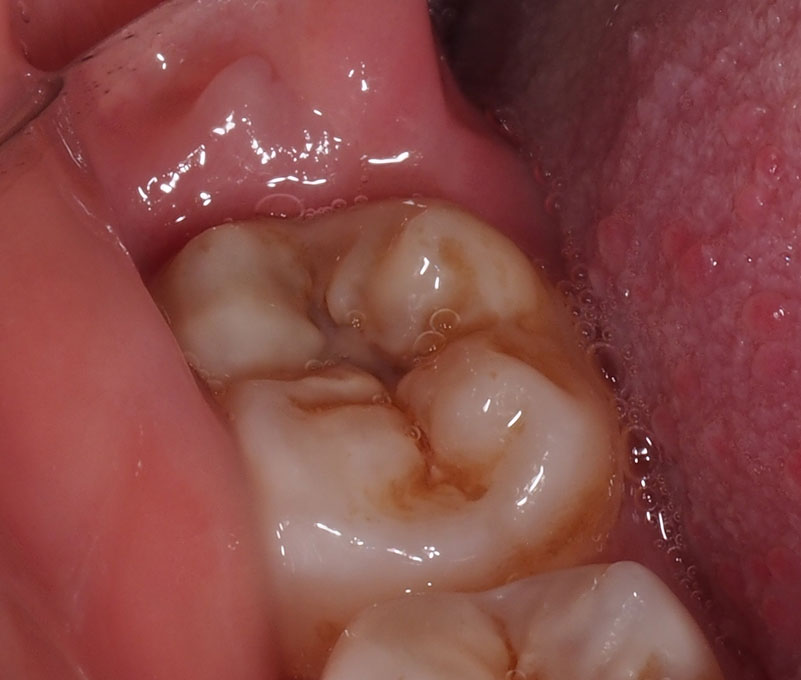

EE presented with recurrent pain and swelling on the lower right side, where the wisdom tooth had been partially erupted for the past 7 years. This was occurring because there was a flap of gum at the back of the tooth which kept getting plaque and bacteria growing underneath:

EE expected to need to have the wisdom teeth removed. After detailed assessment was made, it was found that the wisdom tooth was actually coming up properly aligned and didn’t need removal.